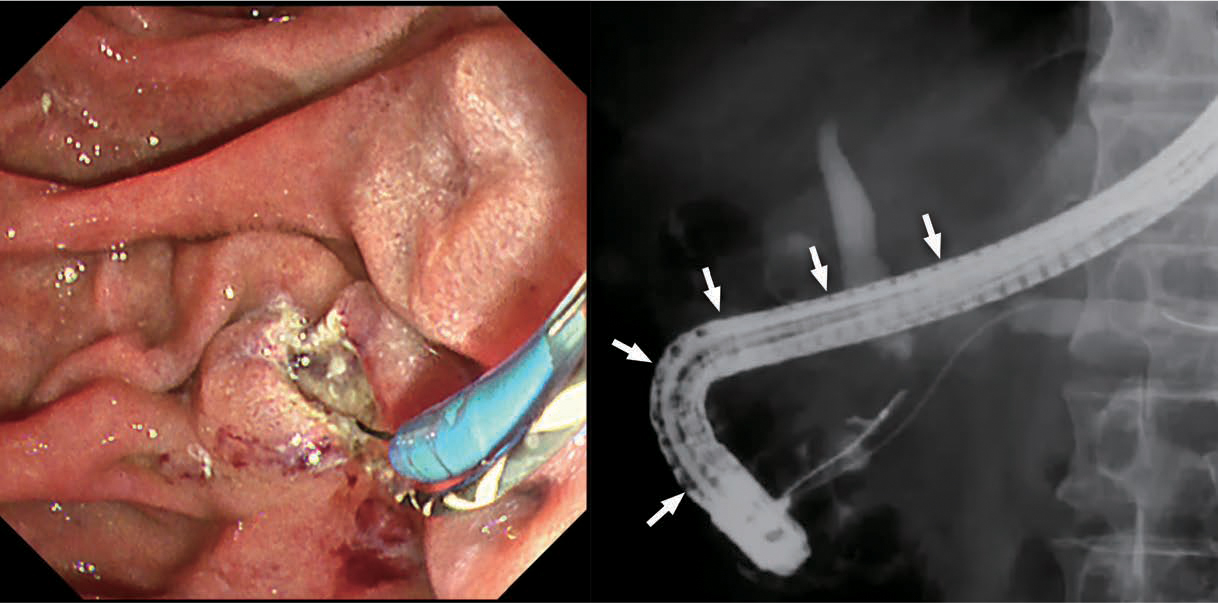

Endoscopist Case Report~Clinical Value of IEE in ERCP~

胆膵内視鏡診療におけるTXI/RDIの有用性~IEEによる視認性向上がもたらすもの~